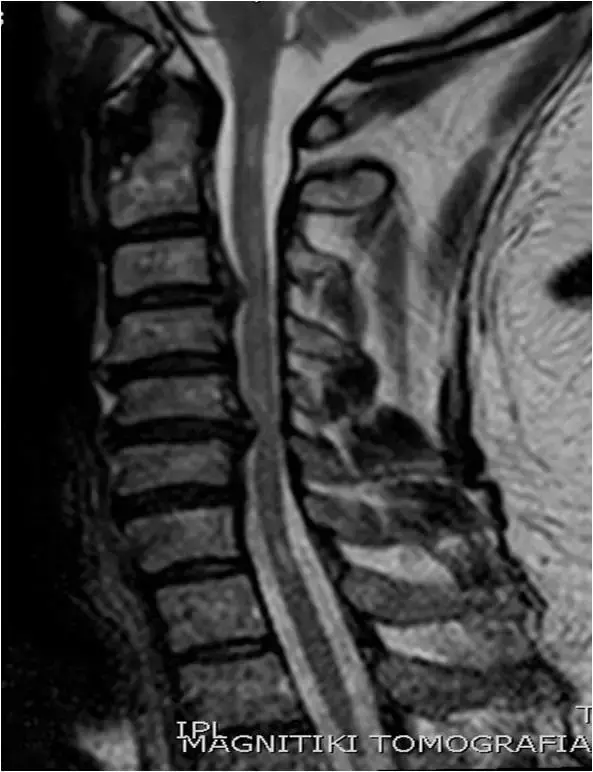

图36:矢状位 T1 TSE图像。 中线部分。生理曲度变直,多个椎间盘向后突出。

图37、矢状位T2 TSE图像。 中线部分。 与图像37相同的患者。颈椎的拉伸。 鉴定出多级椎间盘病变(C3-C4,C4-C5,C5-C6)。